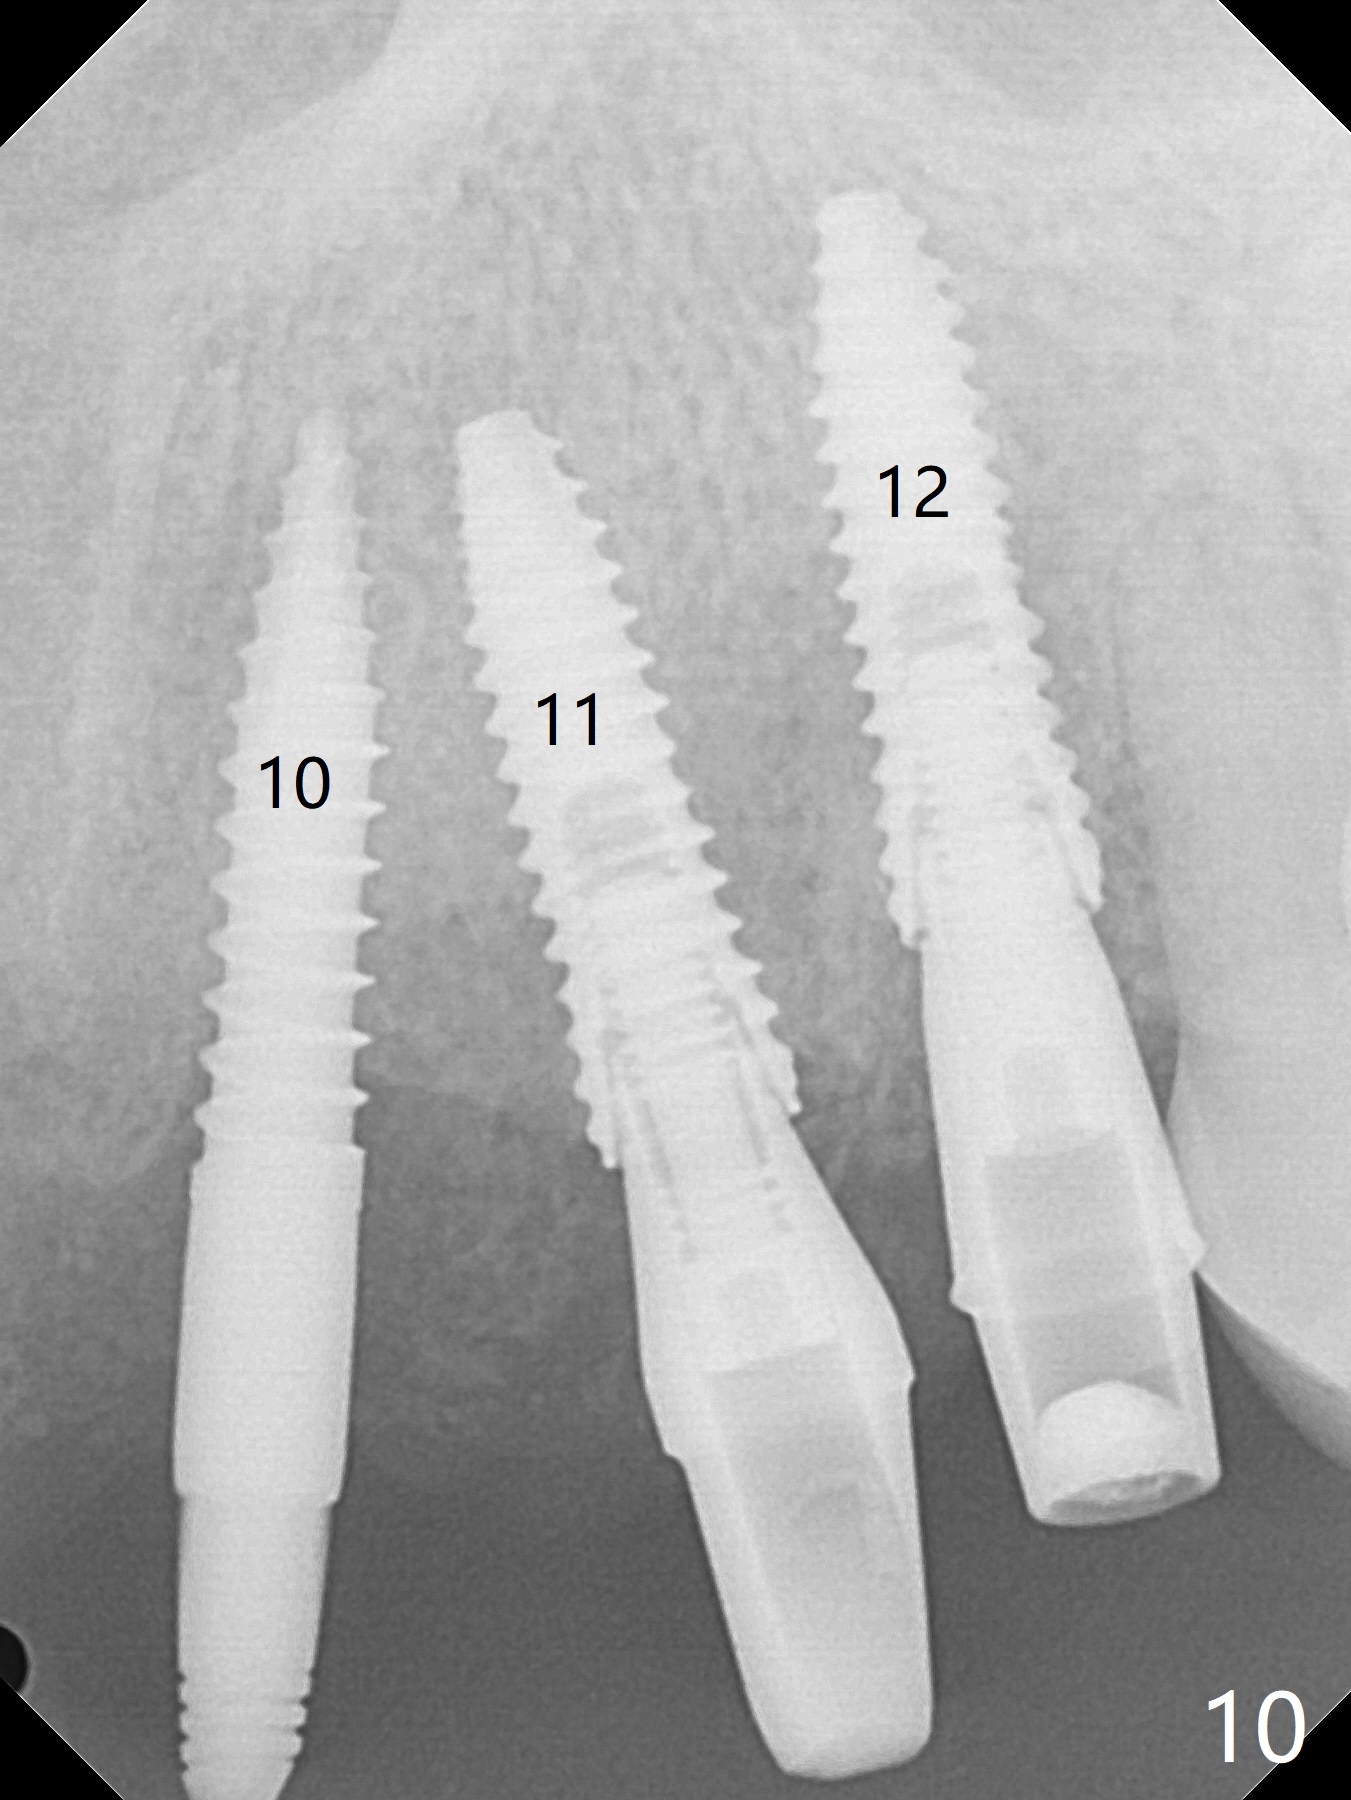

To have enough clearance for the splinted provisional at #6-12 (Fig.1 *), composite has been placed in the posterior teeth (bilateral, *, Fig.2). When the composite is removed, there is no clearance between the implants/abutments of #7 or 10 (Fig.3). Incision is made with removal of the 1-piece implant at #7; there is enough bone to move the osteotomy buccal (Fig.4 arrowhead). When the same implant is placed buccal (Fig.5), there is sufficient clearance for restoration (Fig.6 *), while there is still enough buccal bone left (Fig.7). When the patient returns 5.5 (for #7 and 10)/6.5 (#6,11,12) months postop, his chief complaint is tenderness lingual to #11. In fact, the abutment screw is loose at #11, while the implant at #10 has mobility (Fig.8), which is related to loss of the posterior stops (*) due to wear. There is slight bone loss mesial to #10 implant 5.5 months postop (Fig.10, as compared Fig.9). CBCT taken 5.5/6.5 months postop shows no bone loss (Fig.11-15). The 3x14 mm 1-piece implant at #10 is mobile 9 months postop and is removed and replaced by a 3.5x13 mm 2-piece one with slightly buccal osteotomy (Fig.16). PAs are taken prior to impression (Fig.17,18). The abutment at #12 is loose (<). More composite needs to be added to the occlusal surface of the upper posterior teeth. Finally the patient agrees to have crowns for the upper posterior teeth.